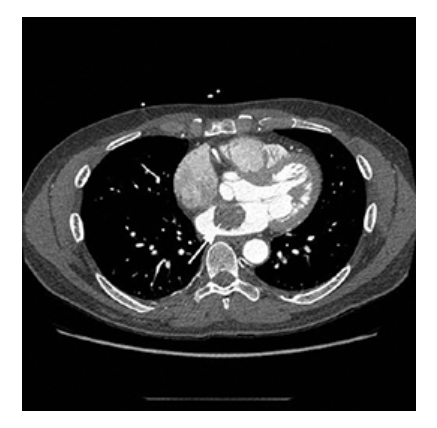

Atrial Myxoma. Contrast-enhanced axial CT shows a round filling defect/mass in the left atrium consistent with a myxoma (arrow).